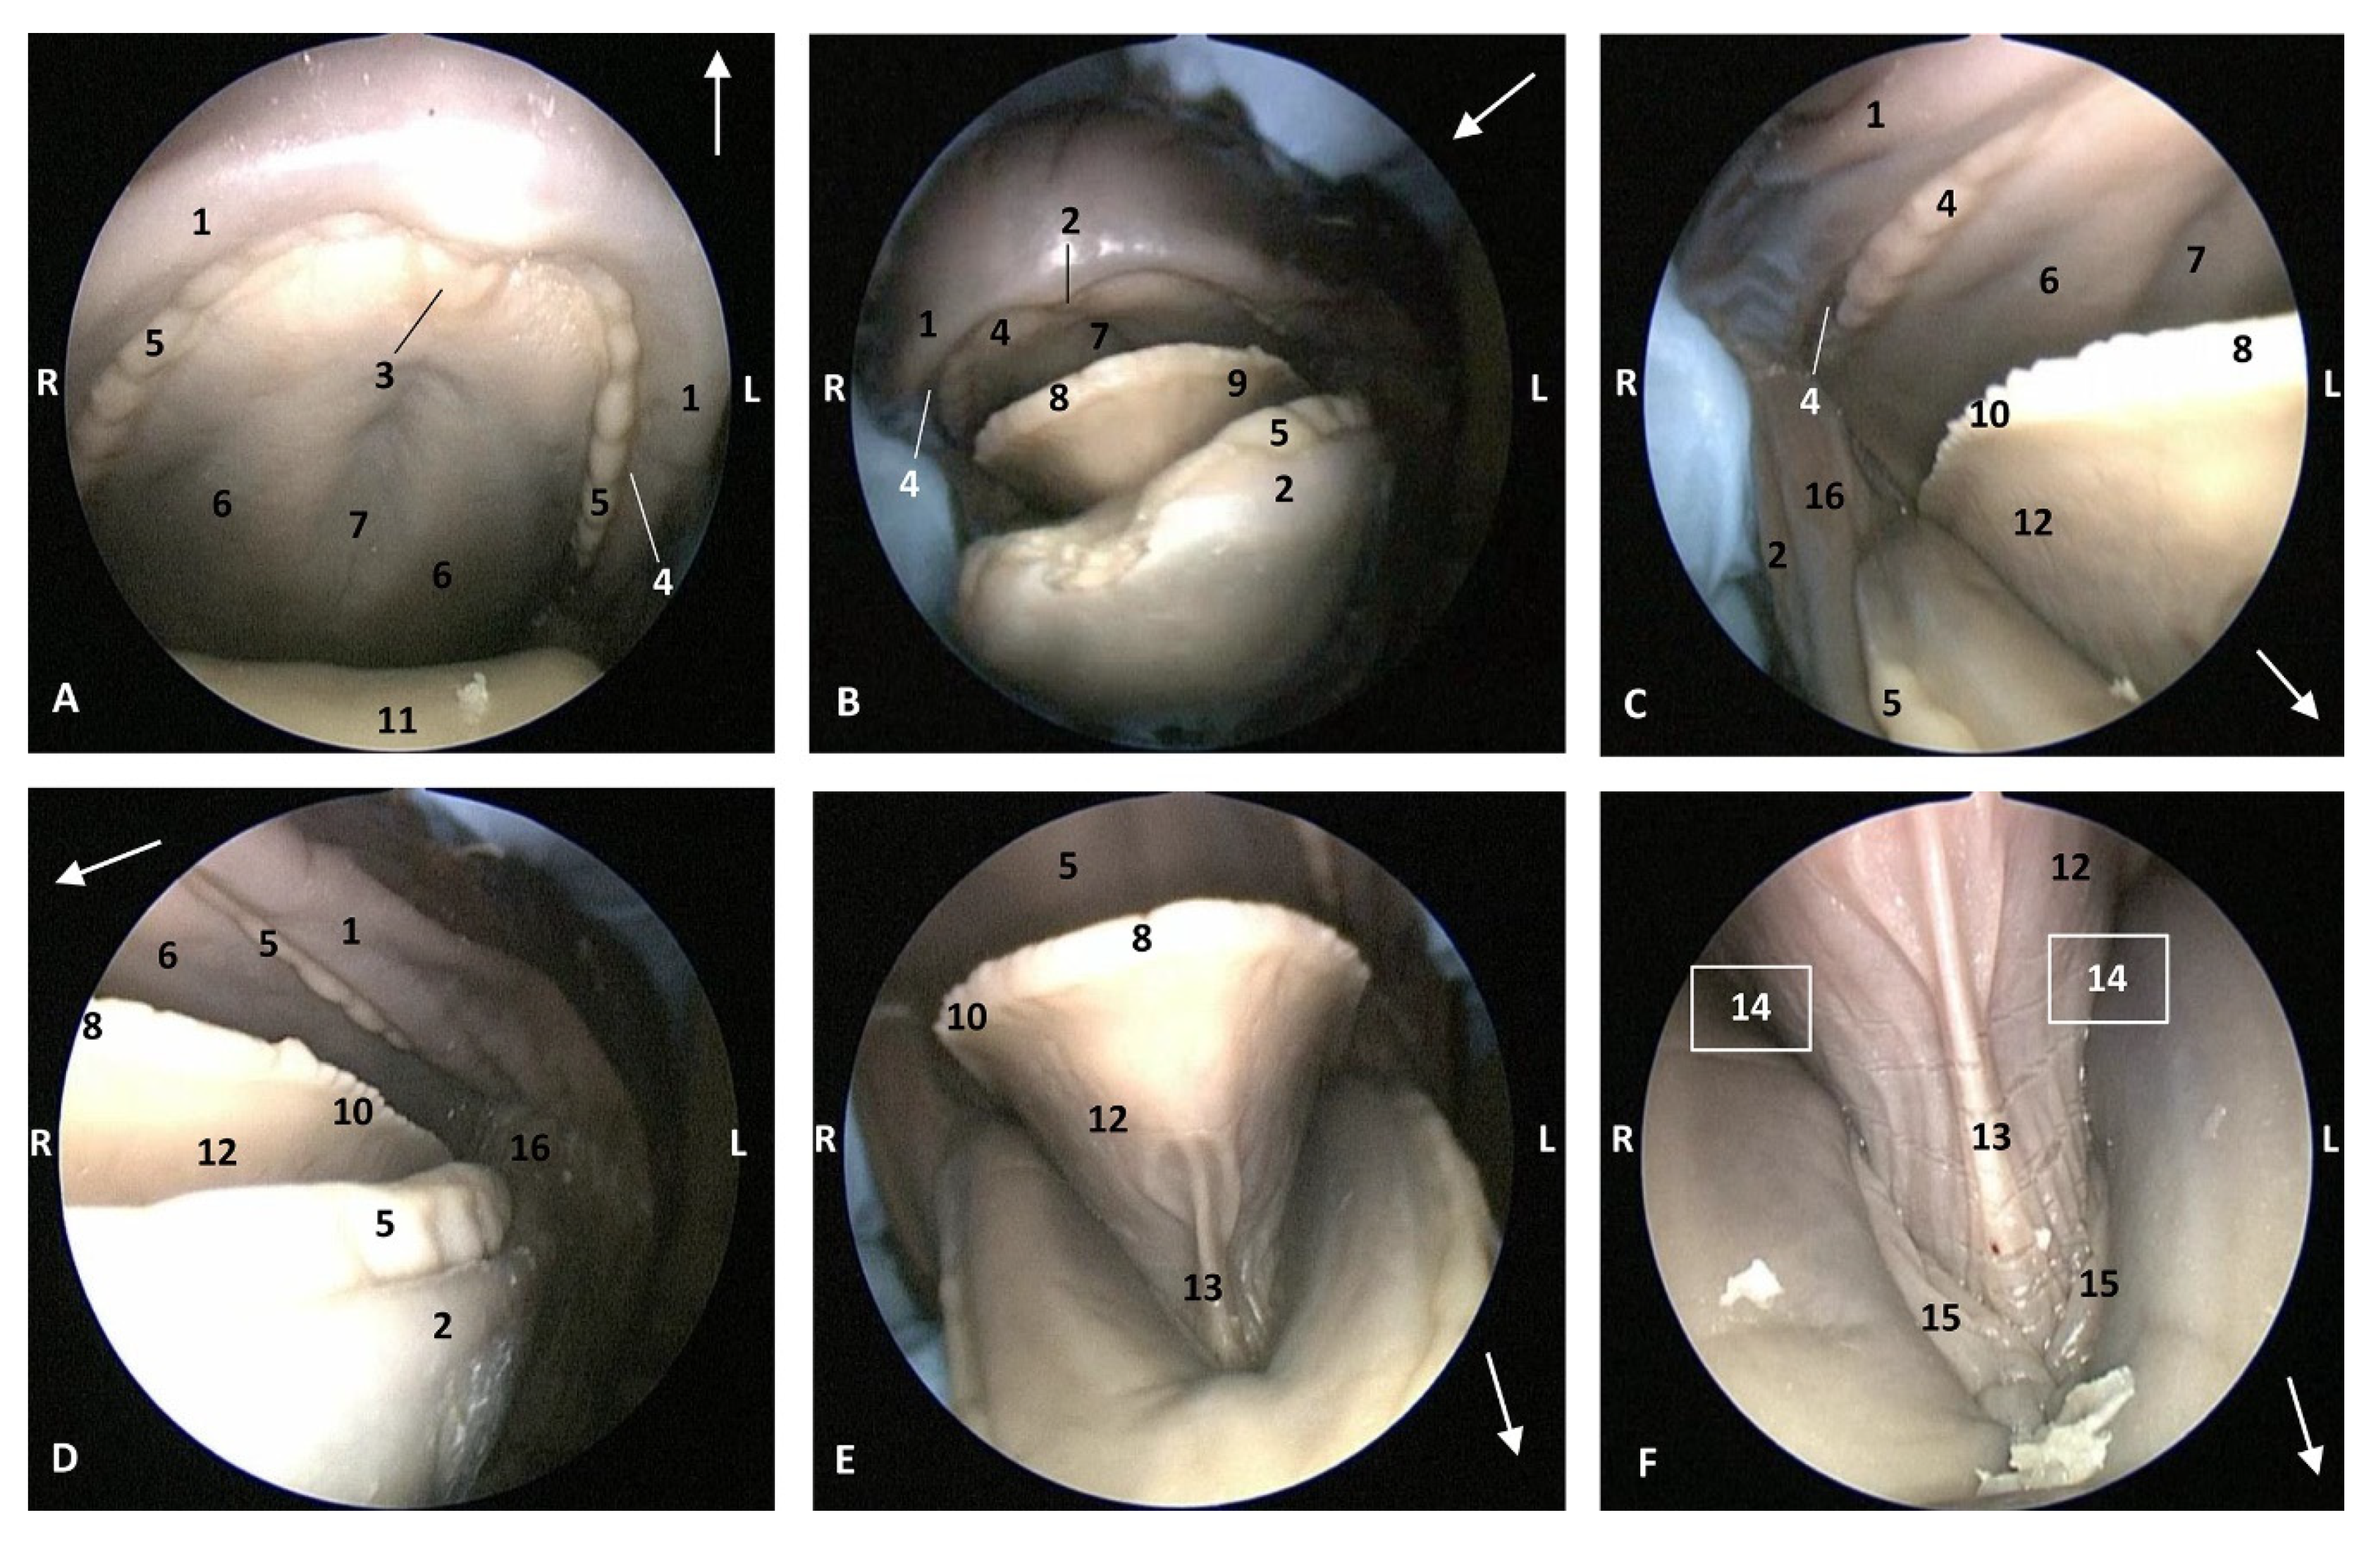

Histological Study

The histological results show that the epidermis of the oropharynx at the soft palate level has a tightly papillary stratum with deep mucous glands and abundant mucous glands in its submucosa. Additionally, at the level of the isthmus of the fauces, histology shows a connective tissue stratum deep to the epidermis, containing many deep mucous glands (Figure 24A,B). The nasopharynx shows a respiratory mucosa with an anfractuous papillary stratum, below which is a wide connective stratum, and finally a deep serous gland close to striated muscle. Additionally, we have located Vater–Paccini corpuscles near the auditory duct between striated muscles (Figure 24C–E). No lymphoreticular tissue was observed.

Figure 24.

(A,B) Histological study of the pharyngeal cavity. (A) Fauces: soft palate. (B) Tongue: root. (C) Pharynx: mucosa (D,E). Detail of pharyngeal mucosa. Adult, scomu6. 1, Epidermis; 2, Papillary stratum; 3, Secretor ducts; 4, Connective tissue; 5, Deep mucous glands; 6, Deep serosa glands; 7, Vater-Paccini corpuscle.

MRI Study

The MRI sagittal images show a pharyngeal cavity in a Globicephala melas fetus (gma1) and we could appreciate the oropharynx (fauces), the nasopharynx and the oesophageal vestibule hypointense in both T1 and T2 sequences(Figure 25A,B). Coronal T1 and T2 sequences show the piriform recess alongside the larynx (Figure 25C,D).

Figure 25.

Images of the oral and pharyngeal cavity. MR sagittal and coronal images are oriented so that the rostral is to the right. (A) T1 SE sagittal, (B) T2 FrFSE sagittal, (C) T1 SE coronal and (D) T2 FrFSE coronal planes. 5 months, gma1. 1, Hard palate; 2, Tongue; 3, Oral cavity (closed); 4, Oropharynx: fauces; 5, Oropharynx: soft palate; 6, Laryngopharynx: left piriform recess; 7, Laryngopharynx: oesophageal vestibule; 8, Epiglottis cartilage; 9, Epiglottic vallecula; 10, Arytenoid cartilages; 11, Nasopharynx; 12, Larynx.

3.2.2. Special Study of Nasopharynx and Pharyngeal Diverticulum of the Auditory Tube (PDAT)

In MRI, we can appreciate, in early fetal stages, a bilateral structure within the laryngopharyngeal cavity, each named as a pharyngeal diverticulum of the auditory tube (PDAT). These are connected through the musculotubaric channel with the middle ear (temporal bone: petrous and tympanic part). In a young Delphinus delphis fetus (dde3), it appears in sagittal sections as a hyper/hypointense area seen caudal and rostrally, respectively (Figure 26A,B), and also in coronal sections (Figure 26C,D).

Figure 26.

Images of the pharyngeal cavity. MR sagittal and coronal images are oriented so that the rostral is to the right. (A) T1 SE sagittal, (B) T2 FrFSE sagittal, (C) T1 SE coronal and (D) T2 FrFSE coronal planes. 4 months, dde3. 1, Inner and middle ear; 2, Pharyngeal diverticulum of the auditory tube.

In older Delphinus delphis fetuses (dde5, dde8, dde11) this double space at both sides of the laryngopharynx is more evident and shows the same intensity, but now we can distinguish the vascular area (hyperintense) and the air-filled area (hypointense) (Figure 27, Figure 28, Figure 29, Figure 30 and Figure 31).

Figure 27.

Images of the pharyngeal cavity. MR coronal and sagittal images are oriented so that the rostral is to the right. (A,B) T2 FrFSE sagittal, (C) T1 SE and (D) T2 FrFSE coronal planes. 5.5 months, dde5. 1, Inner ear; 2, Pharyngeal diverticulum of the auditory tube: moderate hyperintense area (vascular); 3, Pharyngeal diverticulum of the auditory tube: hypointense area (air).

Figure 28.

Images of the pharyngeal cavity. MR sagittal and coronal images are oriented so that the rostral is to the right. (A) T1 SE sagittal, (B) T2 FrFSE sagittal, (C) T1 SE coronal and (D) T2 FrFSE coronal planes. 6 months, dde8. 1, Inner ear; 2, Pharyngeal diverticulum of the auditory tube: moderate hyperintense area (vascular); 3, Pharyngeal diverticulum of the auditory tube: moderate hypointense area; 4, Pharyngeal diverticulum of the auditory tube: hypointense area (air); 5, Pharyngeal diverticulum of the auditory tube: hyperintense area (vascular).

Figure 29.

Images of the pharyngeal cavity. (A,B) MR coronal and sagittal images are oriented so that the rostral is to the right. (A,B) T2 FrFSE coronal and sagittal planes. 8 months, dde11. 1, Oropharynx: fauces; 2, Nasopharynx; 3, Laringopharynx: oesophageal vestibule; 4, Nasopharynx: pharyngeal diverticulum of the auditory tube; 5, Pharyngeal diverticulum of the auditory tube: hyperintense area (vascular); 6, Pharyngeal diverticulum of the auditory tube: hypointense area (air); 7, Larynx; 8, Middle and inner ear.

Figure 30.

Images of the pharyngeal cavity. MR sagittal and coronal images are oriented so that the rostral is to the right. (A) T1 SE sagittal, (B) T2 FrFSE sagittal, (C,E) T1 SE coronal and (D,F) T2 FrFSE coronal planes. 4 months, dde14. 1, Inner and middle ear; 2, Pharyngeal diverticulum of the auditory tube (vascular); 3, Pharyngeal diverticulum of the auditory tube (air); 4, Auditory tube; 5, Nasopharinx; 6, Intrapharyngeal orifice.

Figure 31.

Images of the pharyngeal cavity. MR sagittal and coronal images are oriented so that the rostral is to the right. (A) T1 SE sagittal, (B) T2 FrFSE sagittal, (C) T1 SE coronal and (D) T2 FrFSE coronal planes. 9 months, grgr1. 1, Inner and middle ear; 2, Pharyngeal diverticulum of the auditory tube: vascular; 3, Pharyngeal diverticulum of the auditory tube: air; 4, Mandibles.

In more advanced fetal development, it is possible to observe air (hypointense) and vascular (moderate hyperintense) areas, and even the auditory tube (slightly hypointense) (Figure 30).

PDAT were clearly seen in sagittal and coronal sections in a Grampus griseus fetus (grgr1). The T2 sequences are clearer than T1 because they differentiate two areas: slightly hypointense (vascular) and hyperintense (air) (Figure 31).